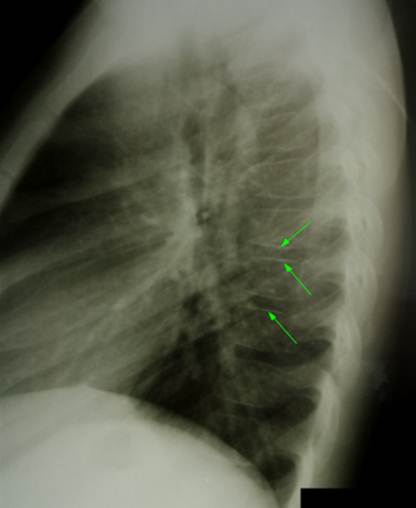

Боковая

рентгенограмма позвоночника здорового мальчика 13 лет, снимок делался по поводу

травмы. Обратите внимание на то, что тени замыкательных пластинок в разных

местах грудных позвонков имеют разную толщину и интенсивность, кое – где

наблюдается разорванность теней апофизарных колец (описываемые явления

обозначены желтыми стрелками). Что же

это, поражение юношеским остеохондрозом? – Нет. Присмотритесь, кажущаяся

картина неравномерности и разрывов апофизарных колец на самом деле связана с

наслоением изображения ребер и легочного рисунка. Кроме того, некоторая разорванность

апофизарных колец имеет место в норме. И самое главное – нет ни одного

хрящевого узла. Просветы между

позвонками ровные и одинаковые. Потому следует быть внимательным при

выставлении рентгенологического диагноза юношеского остеохондроза и

воспринимать видимые изменения в комплексе (хрящевые узлы – склероз

замыкательных пластинок – разорванность апофизарных колец). «Притяжение

за уши» подобного диагноза есть порочная практика, которая, увы, часто

имеет место.